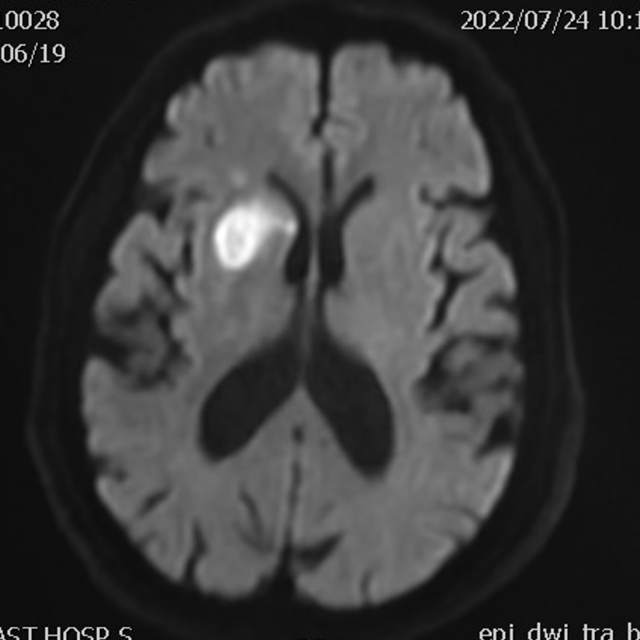

78岁老年男性,最近一个半月来已经和家里人没法正常交流,认知能力大幅下降,在农村,可能也就认为年龄大了,听天由命了。可老人家就是福大命大,有亲戚做医生,间隔17天先后为老人做了两次头颅MRI,发现脑梗塞,右侧血管长节段严重狭窄,右侧大脑半球缺血严重(图6,满江红),手术风险大……,家属经过反复咨询、犹豫、权衡,选择了保守治疗,毕竟老人年龄大了,手腿现在还能动,手术也有风险,时机也不是太好,国外研究不推荐,国内研究也不支持,保守治疗似乎是个不错的选择。然而,保守期间,患者反复出现脑梗塞,认知能力进行性下降,最终促使家属决定采用外科干预。然而,对医生而言,在梗塞的急性期处理这种长节段密布分支血管的病变风险不言而喻,而一味的观望和等候肯定不是最佳选择。过一点,可能出血;欠一点,可能闭塞。全面认真评估后,我们顺利为老人家完成了I期治疗,老人家的“火焰山”(图6)变成了“绿油油”充满生机的田野(图14),缺血明显改善,认知能力大幅提高,术后就能和家人正常交流了,也记起了很多以前忘记的事情……,家人很开心。